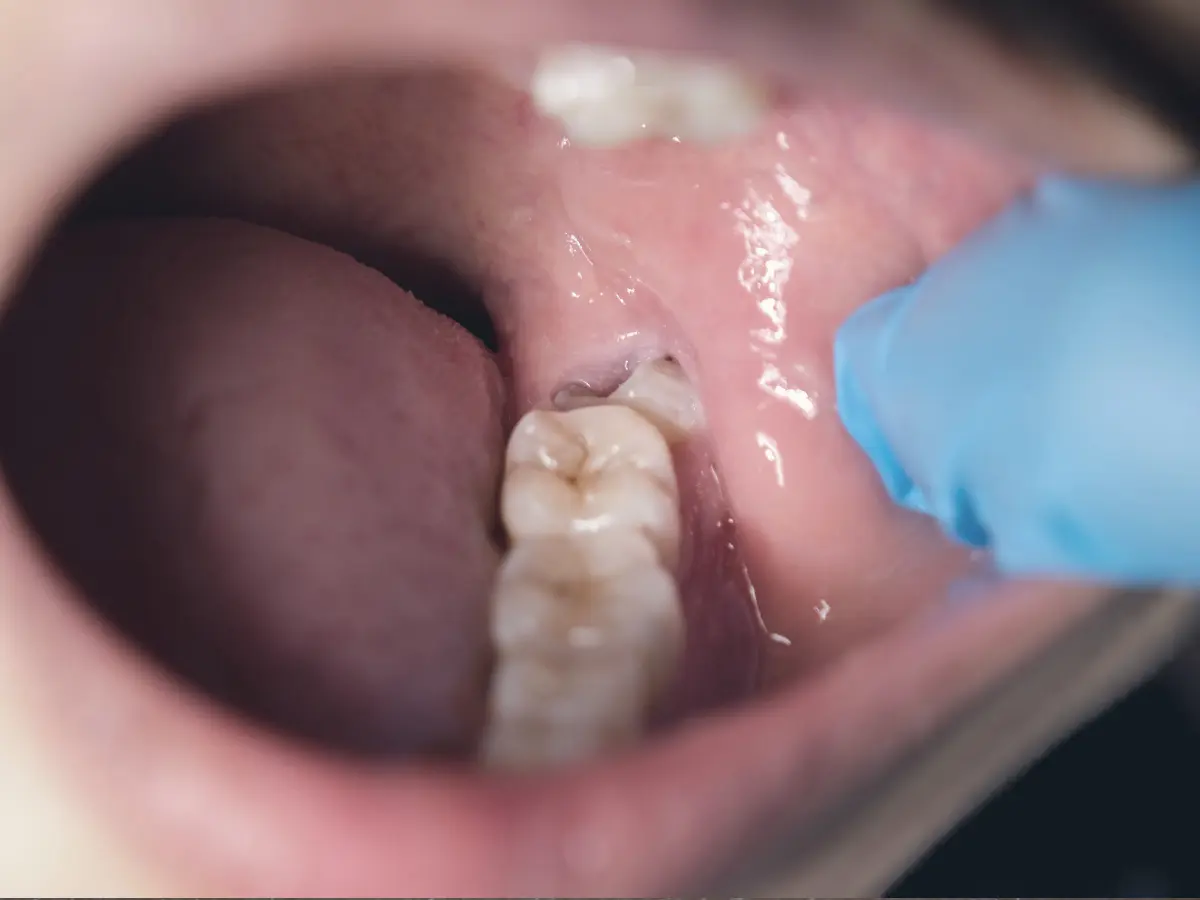

Wisdom teeth are the last molars to come in and often there is not enough space. They can trap bacteria under the gums, push on nearby teeth, or damage the second molar. We use a panoramic X-ray or CBCT to map position and roots before recommending removal or monitoring.

- Pain, swelling, or gum infection around a partially erupted tooth

- Repeated food trapping, bad taste, or gum tenderness at the back

- Impacted teeth close to roots or nerves